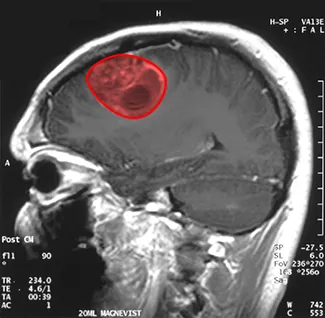

An MRI image of a patient’s brain with a tumor highlighted in red.

Figure 6.47 This magnetic resonance image of a patient’s brain shows a tumor, which is highlighted in red. (credit: modification of work by Christaras A, Wikimedia Commons)

Imagine you are a doctor who has just received a magnetic resonance image of your patient’s brain. The brain has a tumor (Figure 6.47). How large is the tumor? To be precise, what is the area of the red region? The red cross-section of the tumor has an irregular shape, and therefore it is unlikely that you would be able to find a set of equations or inequalities for the region and then be able to calculate its area by conventional means. You could approximate the area by chopping the region into tiny squares (a Riemann sum approach), but this method always gives an answer with some error.

Instead of trying to measure the area of the region directly, we can use a device called a rolling planimeter to calculate the area of the region exactly, simply by measuring its boundary. In this project you investigate how a planimeter works, and you use Green’s theorem to show the device calculates area correctly.